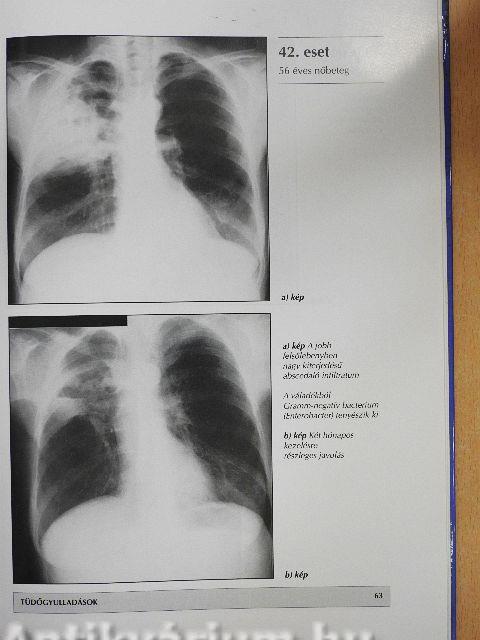

Tüdőgyulladások51

A tüdő tuberkulotikus megbetegedései67